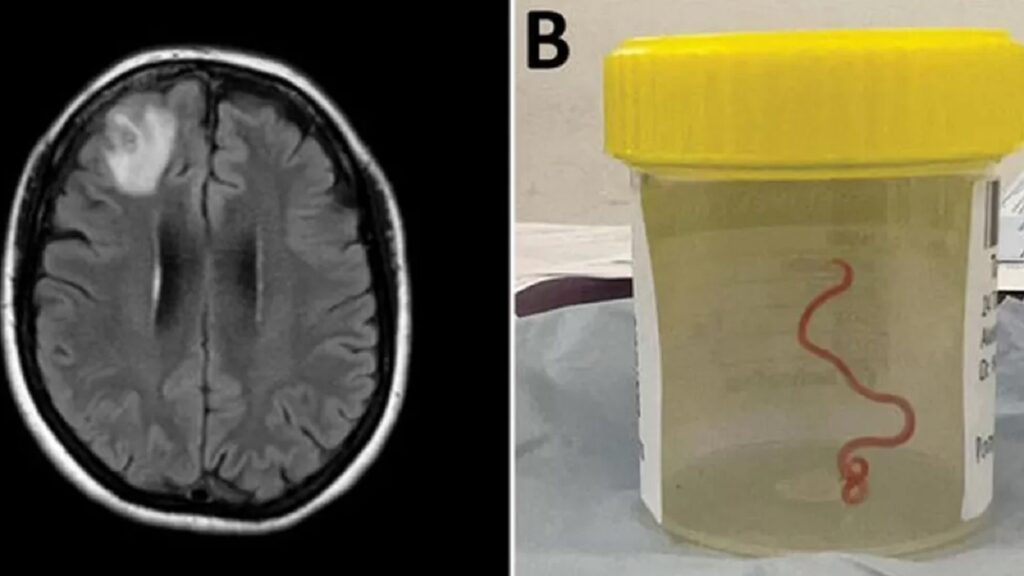

প্রথমবারের মতো জীবন্ত কৃমির সন্ধান মিললো মানুষের মস্তিষ্কে। অস্ট্রেলিয়ার ৬৪ বছর বয়সী এক নারীর মস্তিষ্কে অস্ত্রোপচারের পর বেরিয়ে এলো ৮ সেন্টিমিটারে একটি গোলকৃমি। খবর বিবিসি ও আল জাজিরার।

ভুলে যাওয়ার সমস্যা নিয়ে ২০২১ সালের জানুয়ারিতে হাসপাতালে ভর্তি হন ওই নারী। পরে পরীক্ষা নিরীক্ষার পর সংক্রমণজনিত কারণে তার মস্তিষ্কে অস্ত্রোপচারের সিদ্ধান্ত নেন চিকিৎসকরা। ২০২২ সালের জুনে অস্ত্রোপচার করা হলে আশ্চর্যজনকভাবে পরজীবিটি পাওয়া যায়।

কৃমিটি এখনও জীবিত ও নড়াচড়াও করছে। গবেষকরা জানিয়েছেন, ওই নারী যে এলাকায় বাস করতেন তার আশপাশে অজগরের আবাস ছিল। সেখান থেকে সংগ্রহ করা এক ধরনের ঘাস রান্নায় ব্যবহার করতেন তিনি। বিশেষজ্ঞদের ধারণা, ওই ঘাসের মাধ্যমেই তার শরীরে কৃমি প্রবেশ করেছে।